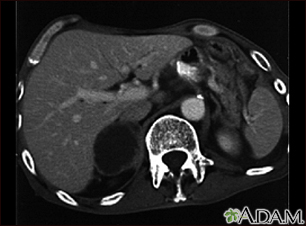

Adrenal metastases - CT scanBackAdrenal metastases - CT scanThis CT scan of the upper abdomen shows an adrenal metastasis (spreading of a tumor to the adrenal gland, above the kidney) in a person with lung cancer. E-mail FormEmail ResultsName:Email address:Recipients Name:Recipients address:Message: